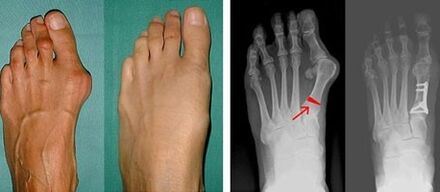

Suure varba ja väikese varba valguse tuvastamise esimeses etapis viib arst läbi visuaalse kontrolli. Sel viisil määrab see patoloogia arenguastme. Liigeste üksikasjalike muutuste tuvastamiseks on ette nähtud röntgenikiirgus ja plantograafia.

Kui visuaalne kontroll ja röntgen ei anna tulemust, suunatakse patsient võimaliku lampjalgsuse kindlakstegemiseks plantograafiale. See meetod hõlmab jalajälgede võtmist, mille alusel tehakse patsiendile ortopeediliste omadustega kingad või sisetallad. Seejärel määratakse patsiendile podomeetria. Selle meetodi abil määratakse inimese kehakaalu surve jalgadele arvutianalüüsi abil. Täiustatud diagnostika tulemused on aluseks esimese ja teise varba kõveruse ravimeetodi valikul.